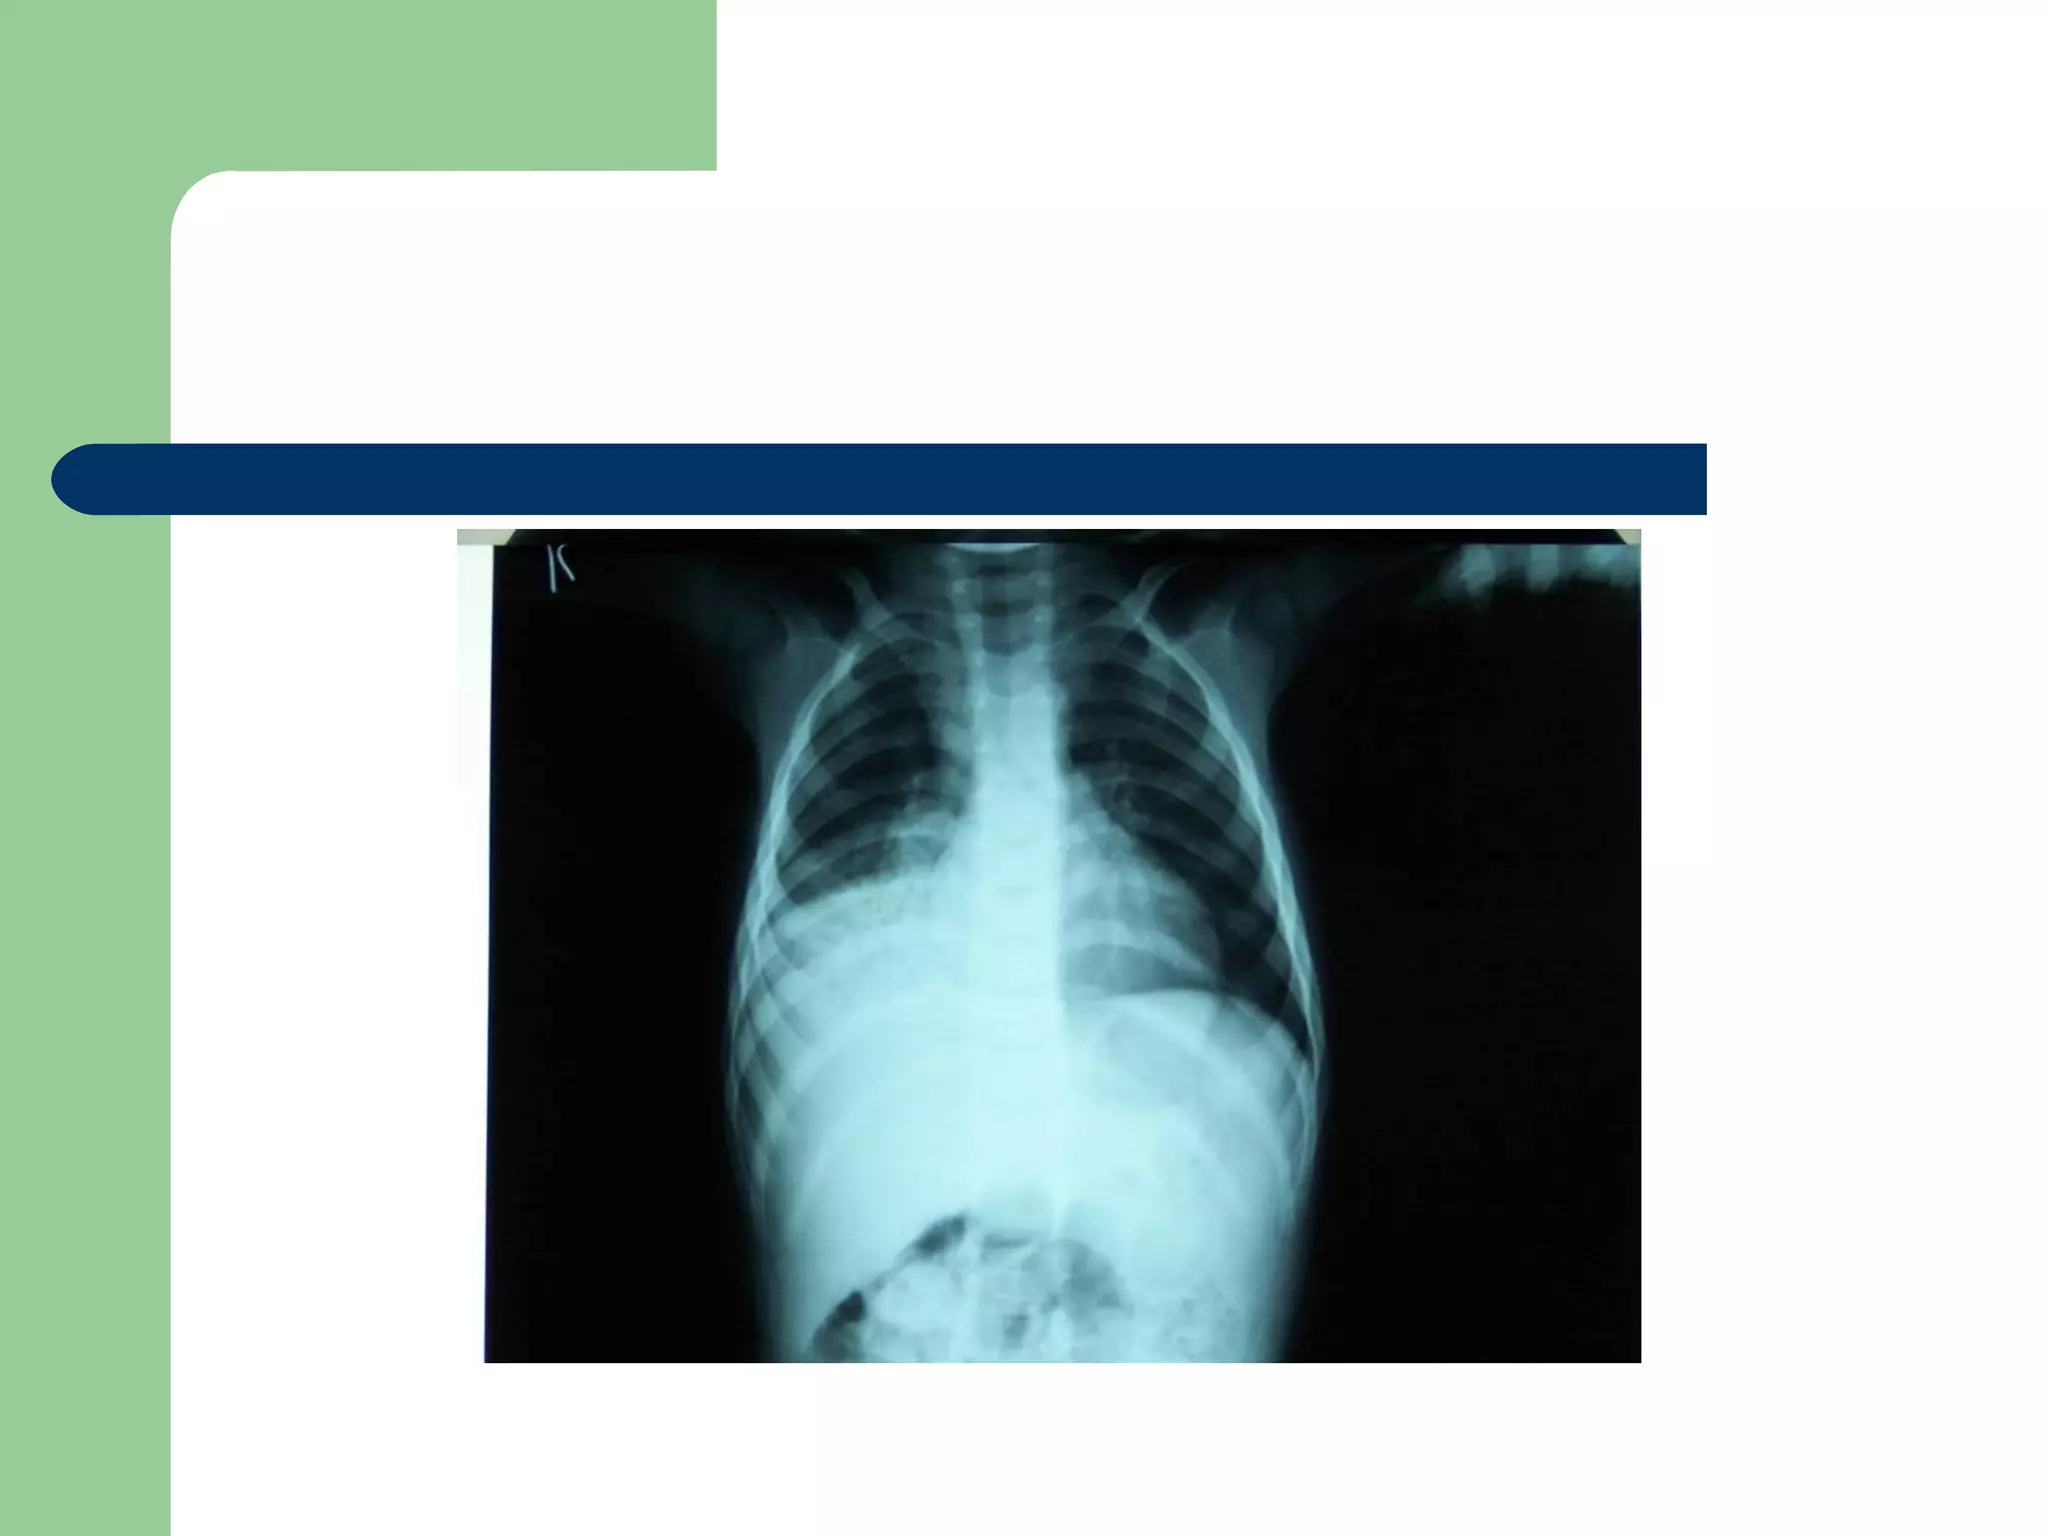

 CXR may be normal if the FB is not radio- opaque.

or it can show a radio- opaque FB such as bone.

Obstructive emphysema: is produced by intra-bronchial

FB that allows air to enter in inspiration and prevents its

exit in expiration.

Lung collapse (complete or partial) is produced by a FB

that blocks the bronchus completely.

Unresolved pneumonic consolidation.

A five and a half yr old boy: non-resolved cough

Of 40 days duration

DIAGNOSIS…  Examination:signs of respiratory distress may be present.  CXR may be normal if the FB is not radio- opaque. or it can show a radio- opaque FB such as bone. Obstructive emphysema: is produced by intra-bronchial FB that allows air to enter in inspiration and prevents its exit in expiration. Lung collapse (complete or partial) is produced by a FB that blocks the bronchus completely. Unresolved pneumonic consolidation. Lung abscess or broncheictasis are caused by a long-standing FB.

A five anda half yr old boy: non-resolved cough Of 40 days duration